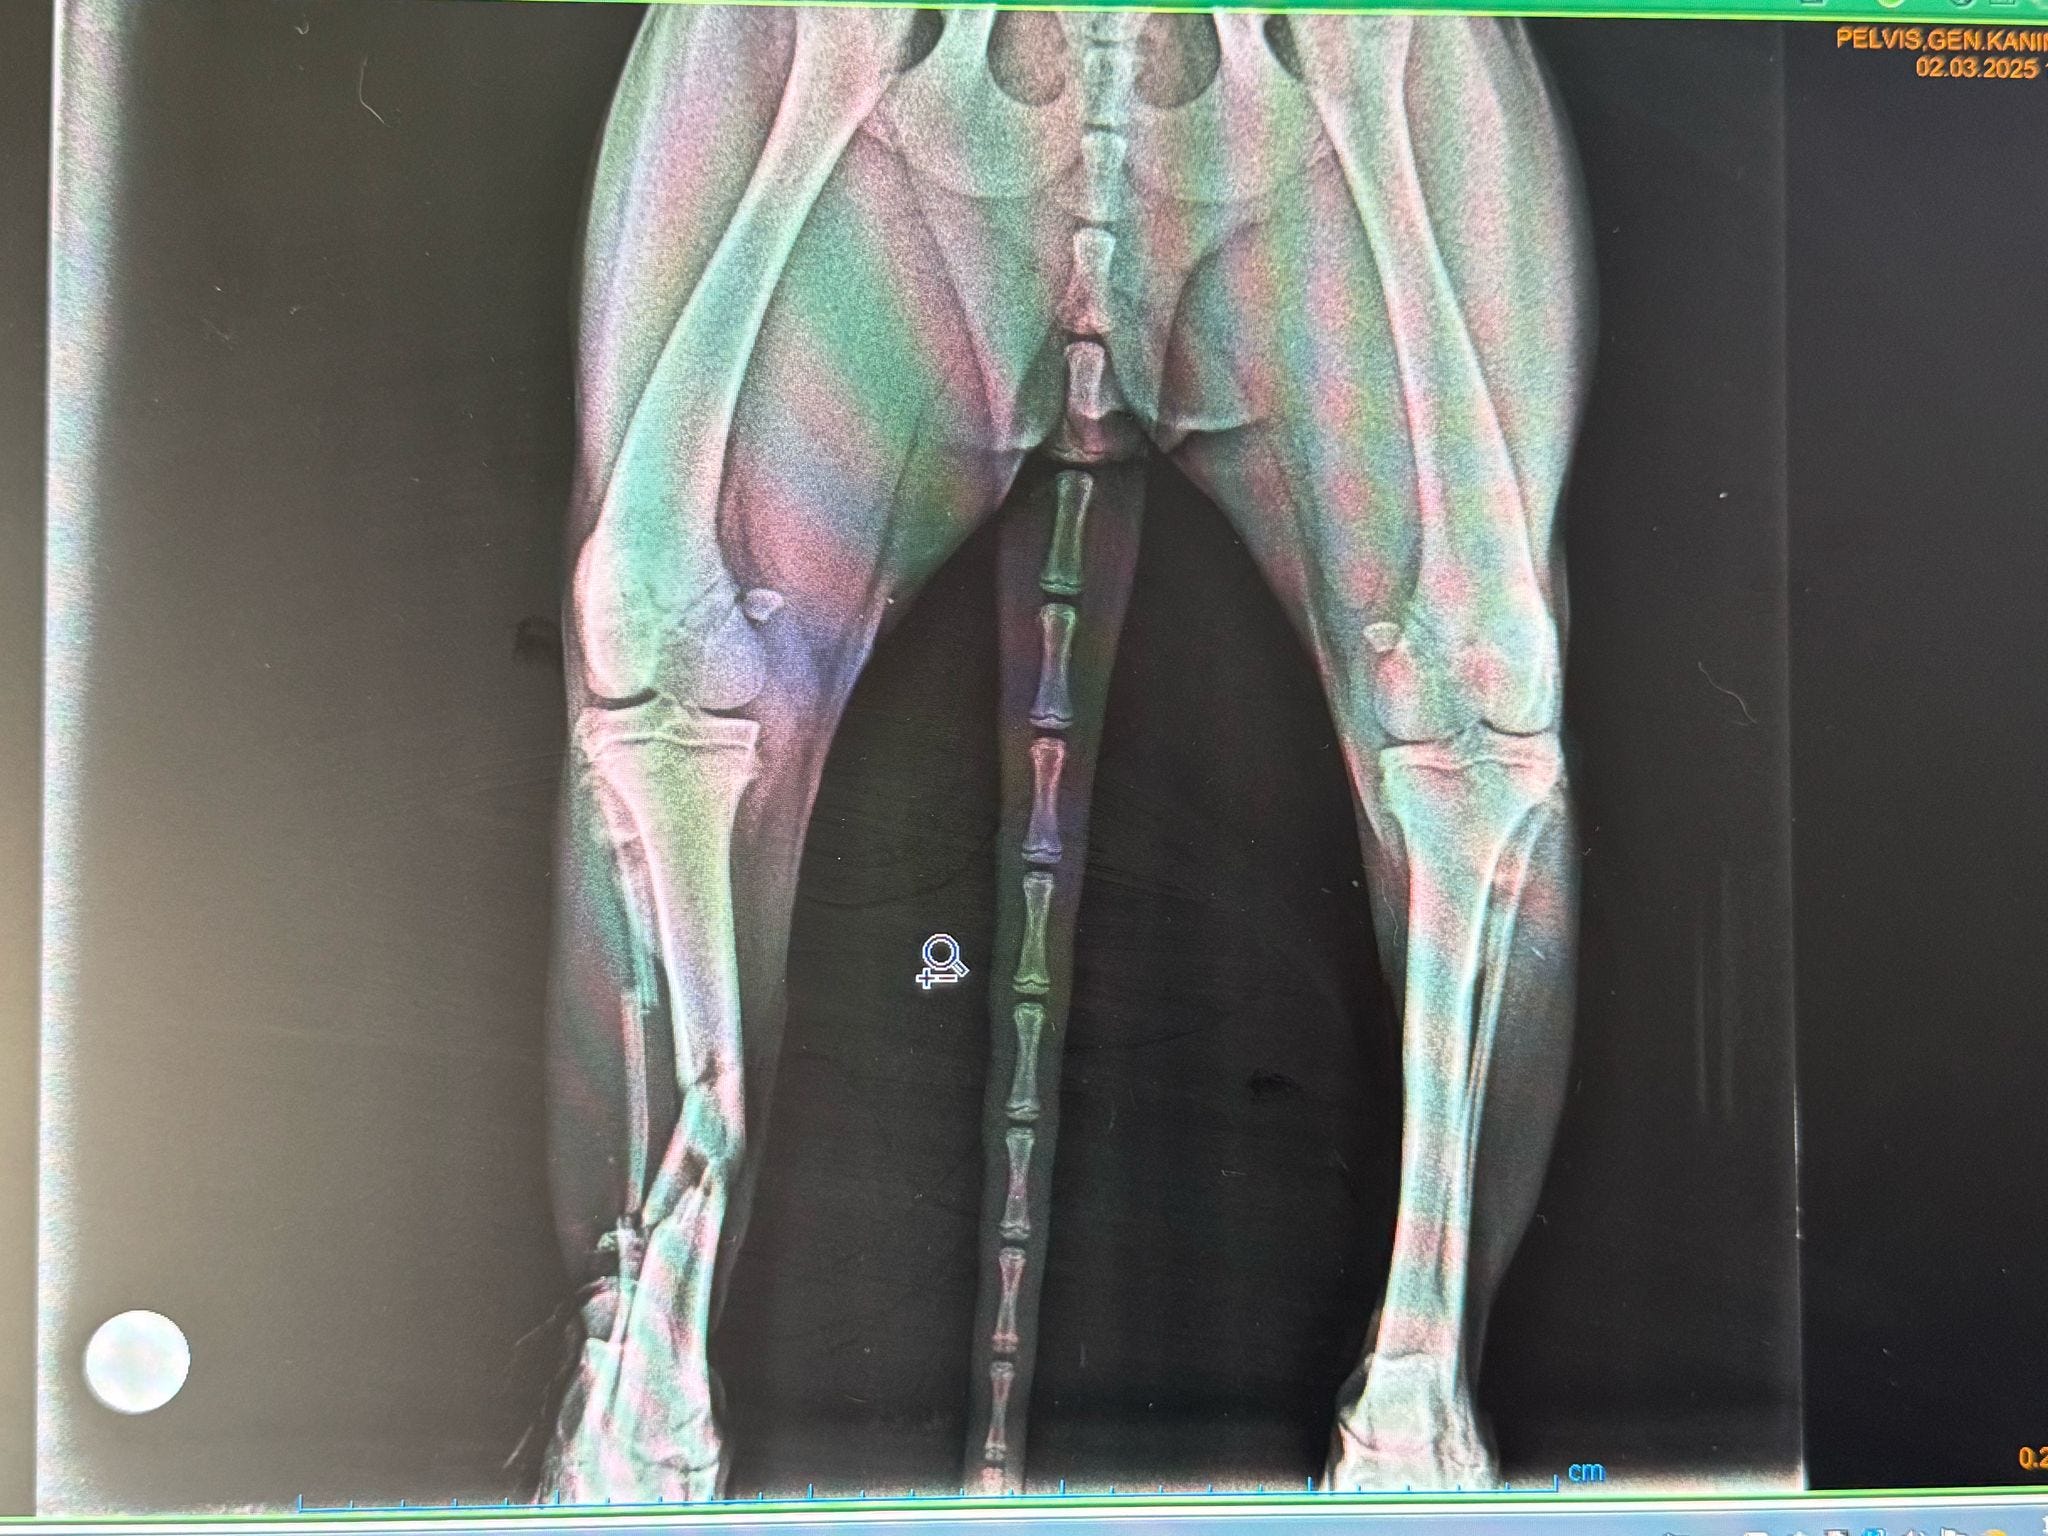

Fractures and Orthopaedic Trauma

Broken bones are one of the most common and most visible consequences of a road accident. Victims may suffer:

Long bone fractures (legs, especially the femur and tibia)

Pelvic fractures, often caused by the force of impact

Multiple fractures, indicating severe, high-speed collisions

These injuries are painful and can lead to shock if not addressed swiftly. Proper stabilisation and immediate veterinary assessment are vital.